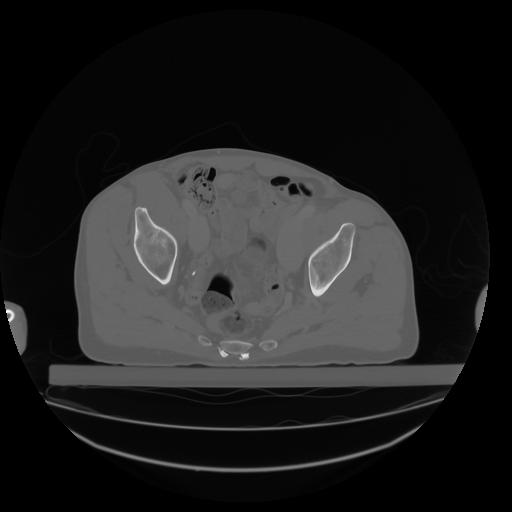

27 CUERPO,CE,Axial,3.0,CUERPO,,